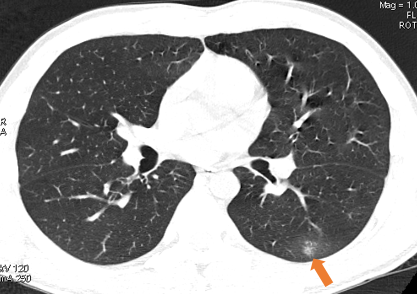

早期新型冠状病毒肺炎在CT图像显示为密度稍高的磨玻璃斑片病灶(箭所示)